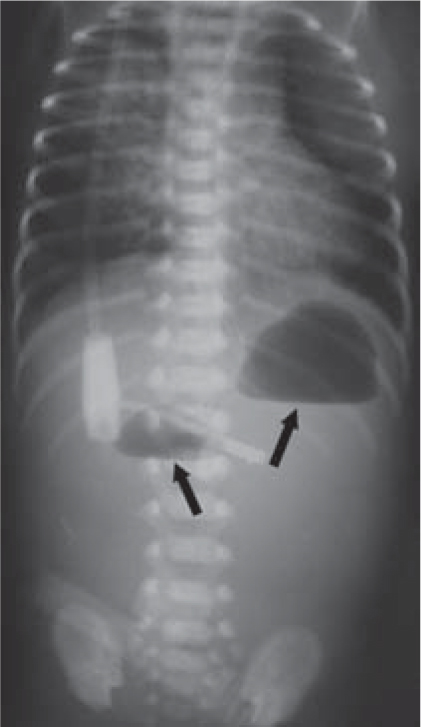

Medical News Radiology Mcqs For Usmle Aipgee And Plab Double Bubble Sign Causes Include A Congenital Obstruction Duodenal Web Duodenal Atresia Duodenal Stenosis Annular Pancreas B

シングルバブル、ダブルバブル、トリプルバブルサインの違い なになにバブルサインとは、消化管が閉鎖される疾患のレントゲン所見のこと。 シングルバブルサイン ダブルバブルサイン トリプルバブルサイン 画像 出典 出典:105D41 出典スクリーン ダブルバブル クリア honda vtr1000f '97 〜 '05 カラー:クリア タイプ:ダブルバブル ご注意 写真は実際の製品と異なる場合がございます。 16年3月22日からの新価格です。Double(ダブル)は、日本の女性 歌手、ソングライター、takakoによるソロ・プロジェクト。 姉妹デュオとして1998年にデビューしたが、1999年に姉のsachikoが急逝したため、以降は現在の形態となった。 06年からはdj lilly aka double(ディージェイ・リリー・エーケーエー・ダブル)名義

bubble バブル の値段はいくら? 今回はTWICEの画面で紹介するけど bubble バブル のアプリから値段を確認できるよ。 ここで注意したいのが、bubbleの登録はNiziUメンバー1人の値段ね。でも複数メンバー登録すると割引もあるよ。ダブルバブルサイン 上部消化管閉塞 十二指腸閉塞 ダブルマドックス杆検査 上部消化管閉塞 先天性消化管異常 メルクマニュアル18版 日本語版 特徴的徴候は,唾液過多,哺乳を試みた後の咳嗽とチアノーゼ,嚥下性肺炎である。 食道 遠 ★リンク